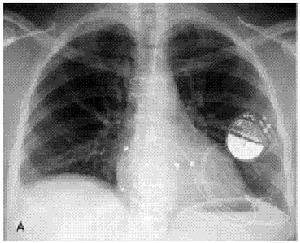

SLE孕婦血中的抗舍格倫綜合徵A、B抗原的抗體,可能還有其他抗體,屬IgG,可穿越胎盤侵入胎體,引起新生兒SLE。由於瀰漫性心肌炎所致的纖維變性健康搜尋,如發生於房室結和His束之間,則可發生先天性房室傳導阻滯(heartblock),而引起Adam-Stokes發作(心傳導阻滯突發、意識喪失或伴有抽搐)或心力衰竭,因而需要安裝起搏器。心傳導阻滯也可發生於胎兒孕婦檢查仍正常,但日後肯定會出現SLE症狀或其他結締組織疾病。MeCune(1987)曾報導24例先天性紅斑狼瘡兒童,其中有12例有心傳導阻滯10例有皮損,2例兩種全具備;3例在新生兒期死亡11例存活中有5例需帶起搏器。子代發病與孕婦妊娠期的病情輕重似無明顯關係。

(2)硫唑嘌呤:近年已較多用於重症病人,且常與潑尼松(強的松)聯用,可增加療效。但已發現IUGR發生率高,新生兒有暫時性淋巴細胞減少,免疫球蛋白合成明顯減低,胸片見胸腺縮小為保全全應慎用或不用。